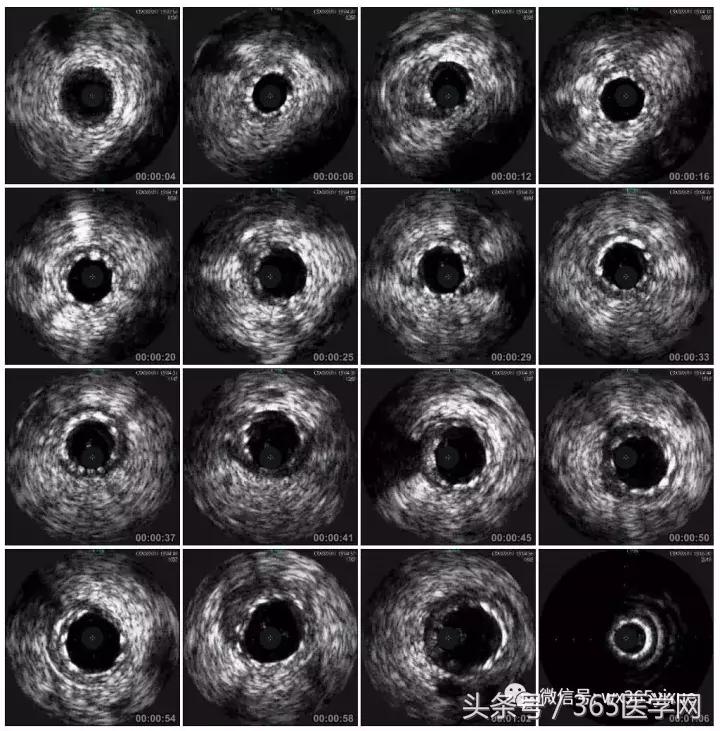

RCA闭塞段球囊扩张后IVUS

支架术后IVUS

小结

CTO介入前要认真读图,详细制定介入策略及步骤,

明确IVUS在CTO介入的重要性,

Guidezilla辅助下的ReverseCART更加高效,

Knuckle导丝技术在CTO介入中的使用。